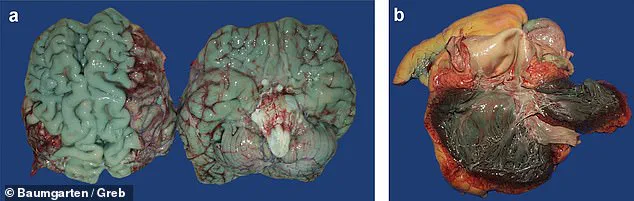

The findings, which emerged during an autopsy on a 72-year-old man whose brain was discovered to be an unusual shade of blue, have prompted a broader investigation into the dye’s effects on human tissue.

The team scoured their database of 15,820 autopsy records spanning two decades and identified 11 cases where organs such as the brain, heart, lungs, and pancreas exhibited a ‘blue-green,’ ‘greenish,’ or ‘turquoise’ hue.

Methylene blue, while historically used for its therapeutic properties, has now revealed a previously unreported consequence: its ability to persist in the body and dramatically alter organ coloration.

Even small doses, as little as 25 milligrams—roughly the size of a quarter of an aspirin tablet—were sufficient to change the brain’s pigment.

In some cases, patients received up to 200 milligrams intravenously over a 10-hour period, and all showed discoloration in the brain and heart.

The researchers emphasized that the blue hue darkened further during autopsies when exposed to air, but this effect was unrelated to the causes of death.

Instead, it underscores how the dye lingers in the body, potentially complicating forensic analyses and medical diagnoses.